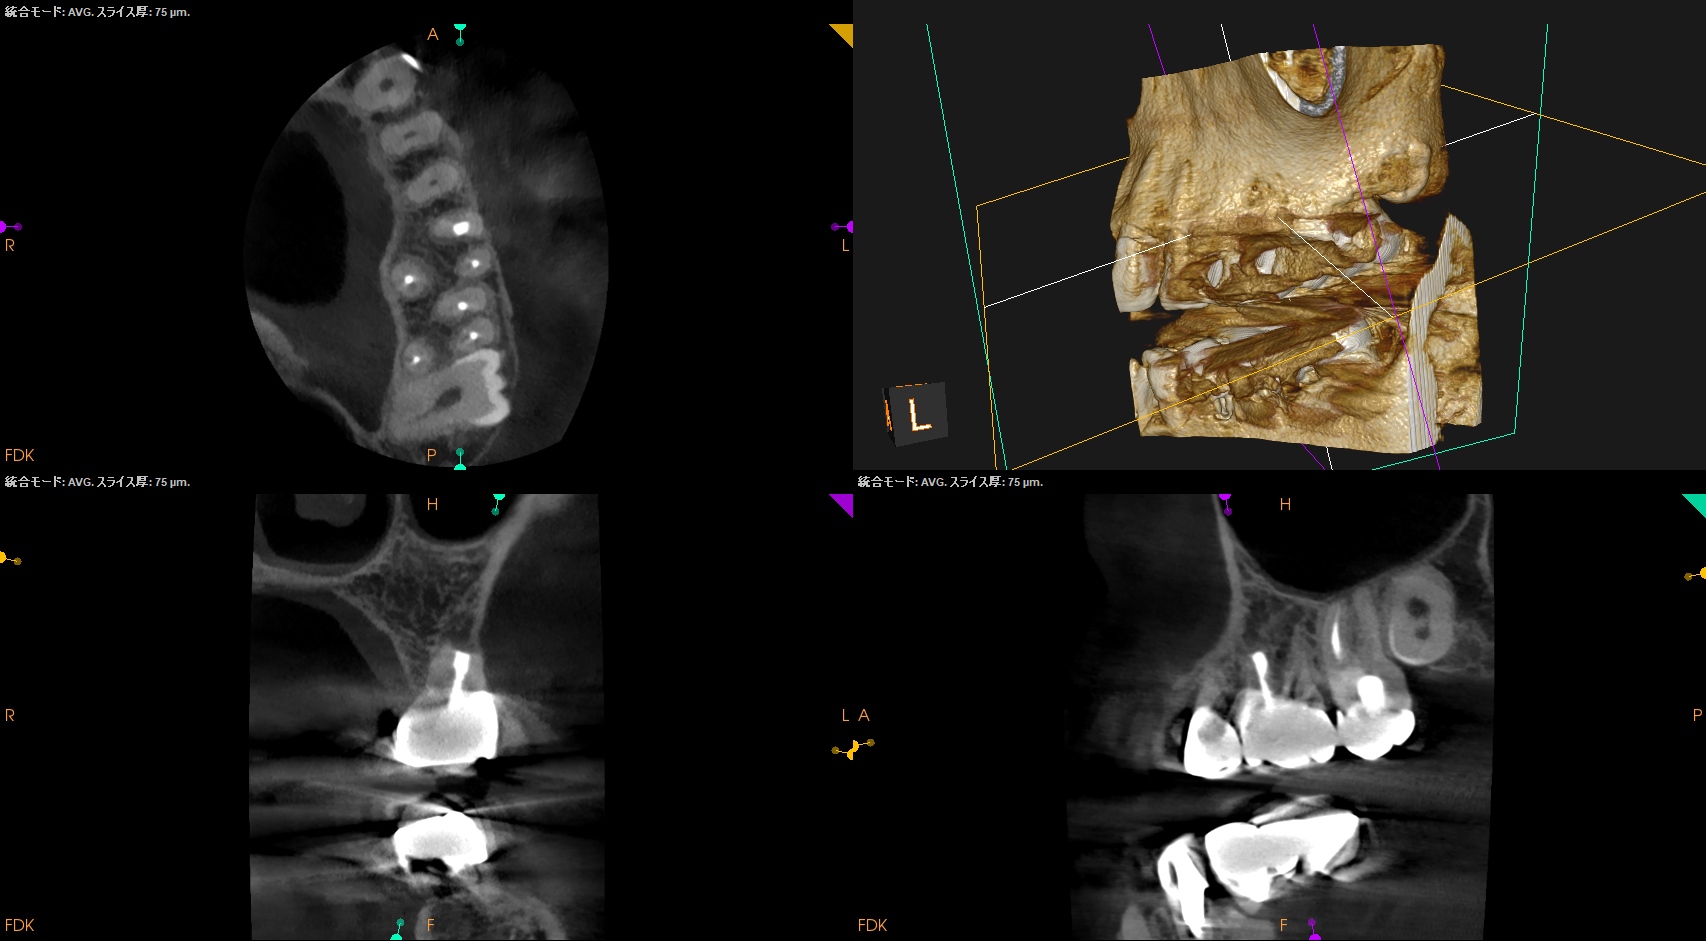

またすでに必要十分に拡大形成がなされていること,

MBの中央にGutta Percha Pointがあることから、MB2はなくMB1のみの処置でいいとわかるところもCBCTの強みである。

さておき、この問題を解決するには再根管治療でなく歯根端切除術であるということがわかる。

その際は、

クラウンのマージンより8.5mmの位置にMBのApexがあり3mm切断するには頬舌的距離が4.6mm必要で、MB2もないというまさにこの歯は奥歯だが、

事実上、上顎前歯のApicoectomy

と言える。